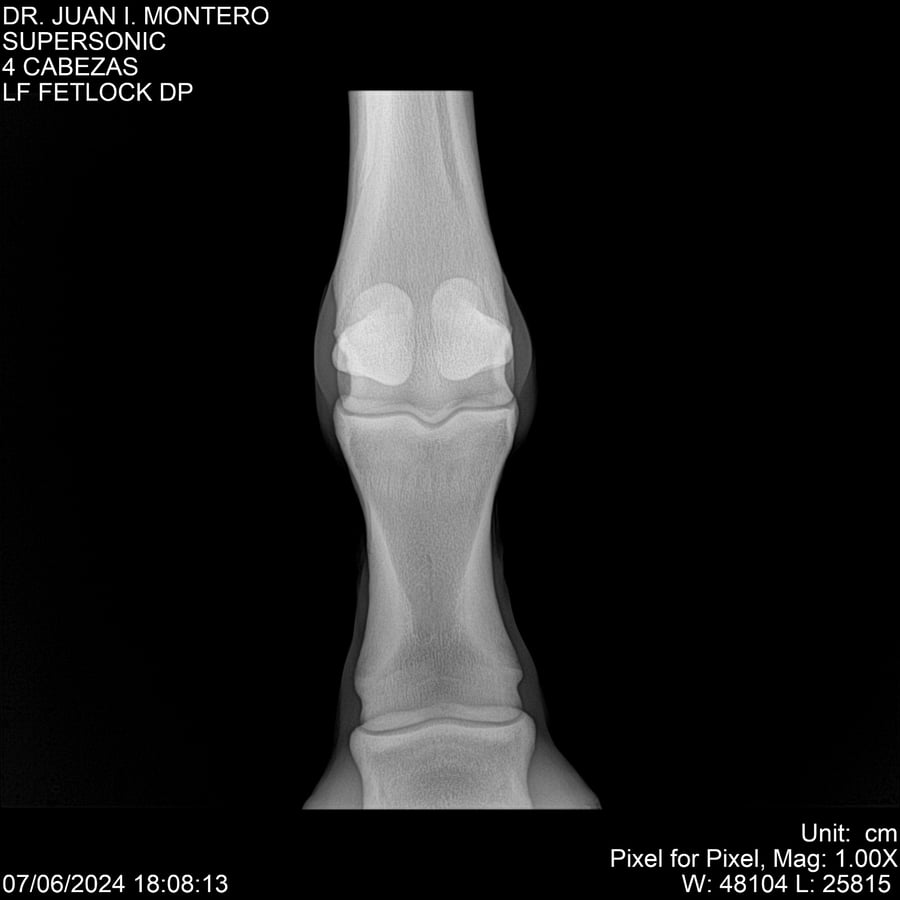

LOTE 5, SUPER SONIC Lote Anterior Volver al remate Lote Siguiente Ficha Contacto Montevideo - Ficha del Lote Identificador: #281089 Categoría: Yeguarizos Montevideo - 69 Visualizaciones ClicData Contacto Empresa: Abelenda N. R., Walter Hugo Nombre*: Teléfono* : E-mail* : Mensaje Enviar Registrese gratis Este contenido Exclusivo está disponible sólo para usuarios registrados Ingresar